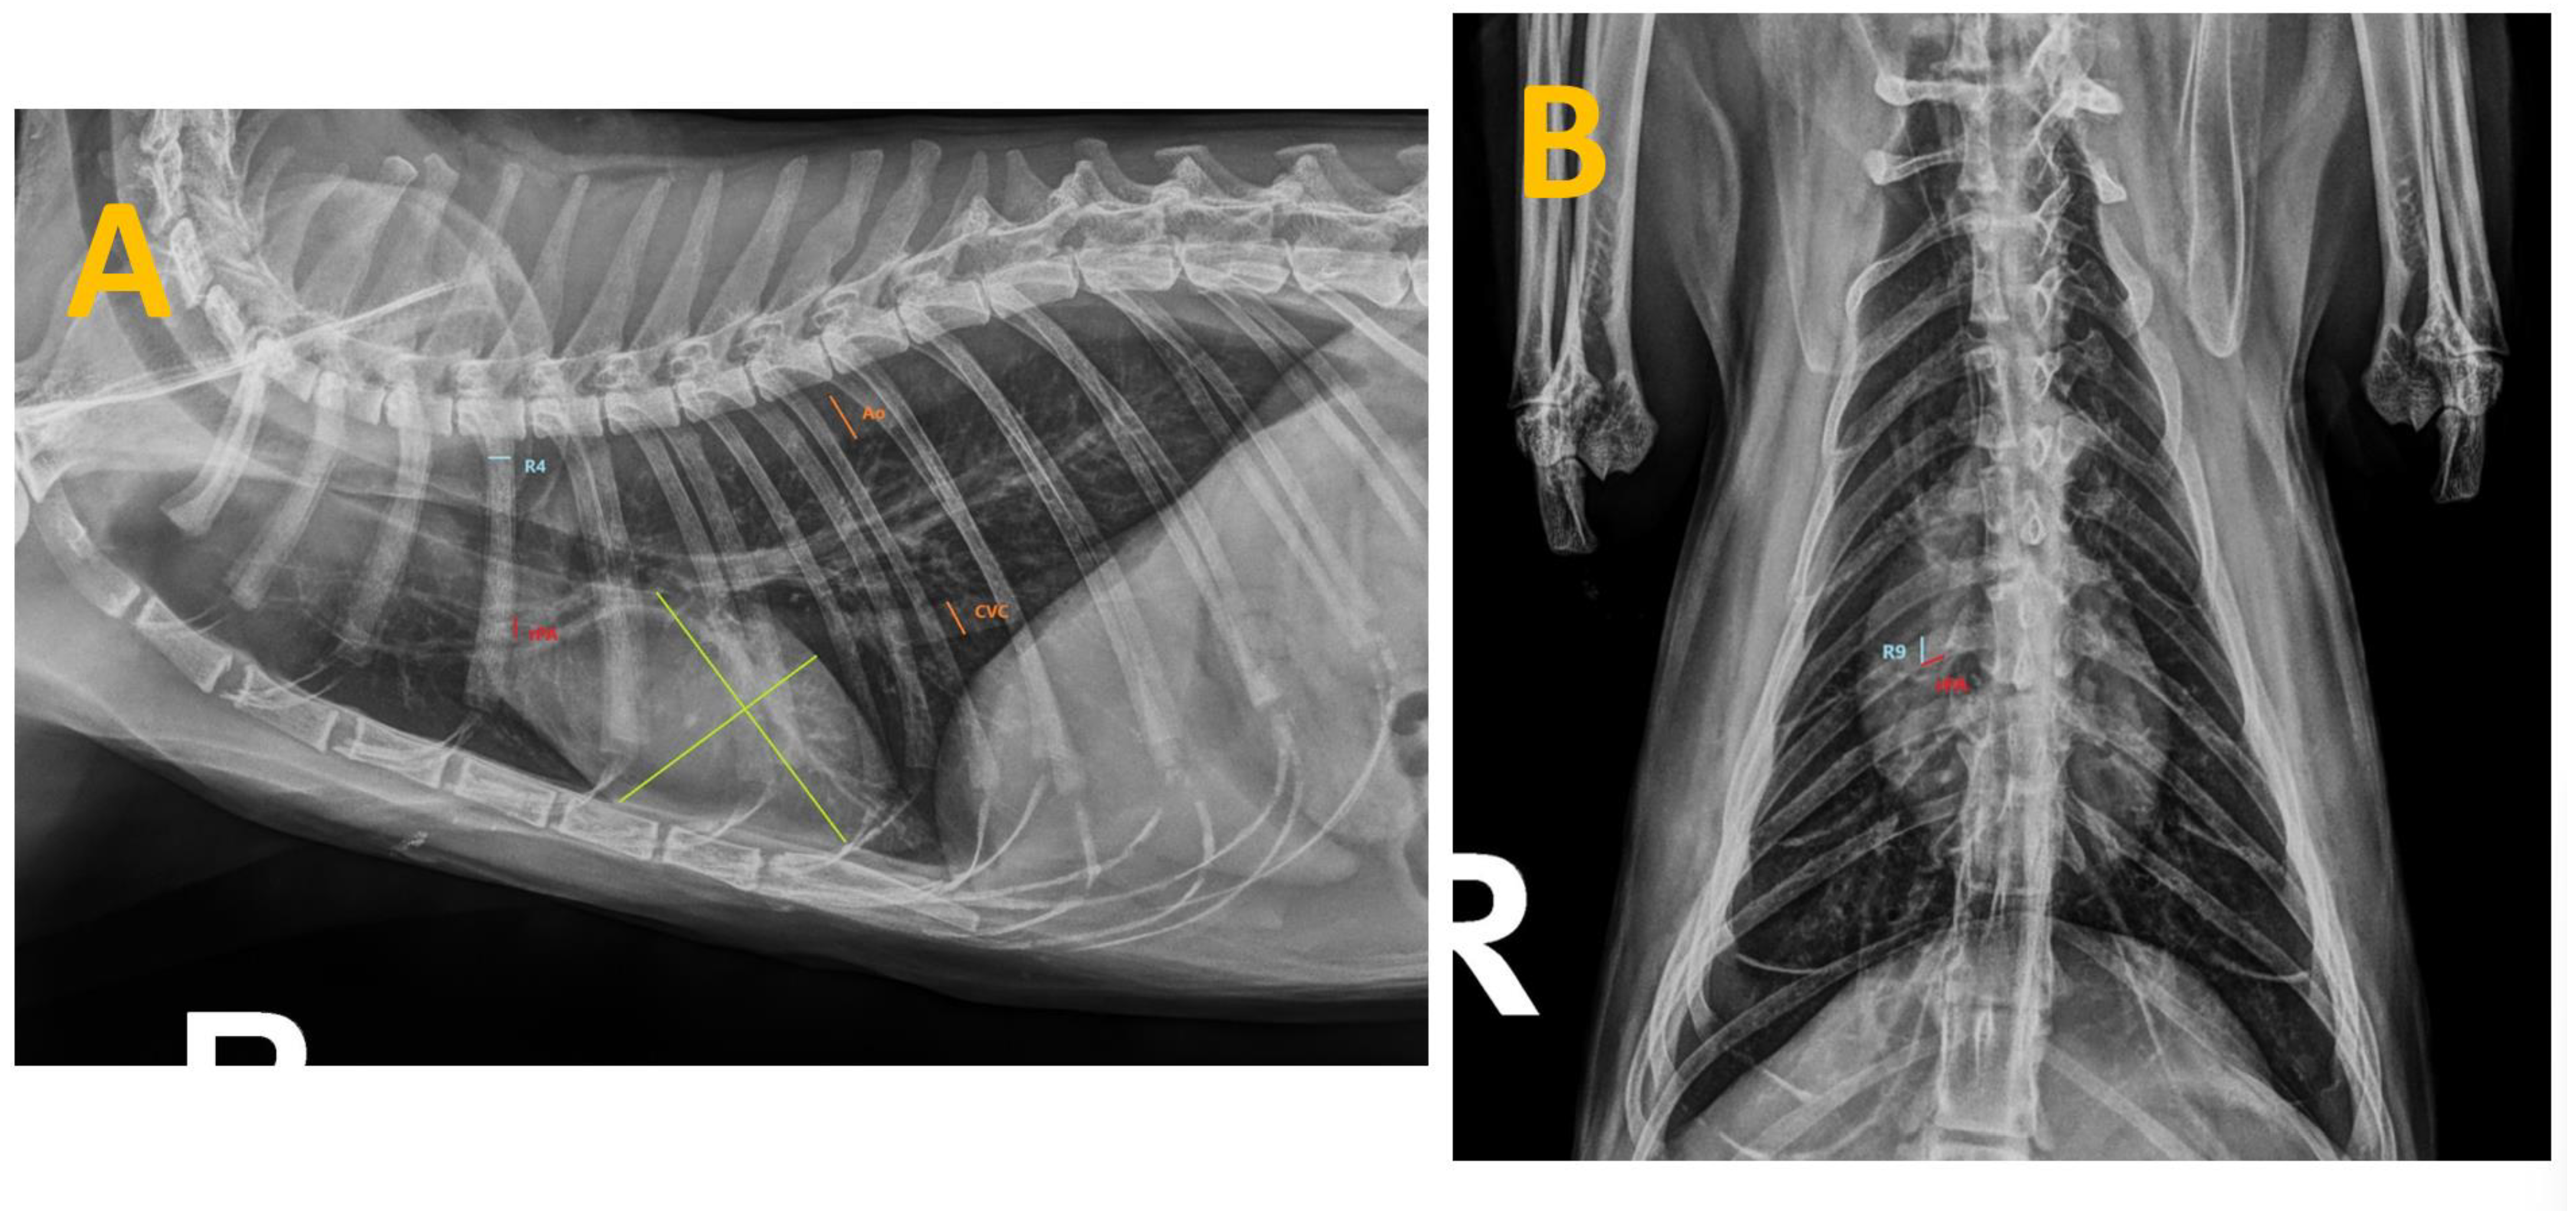

| CrPA/R4 | Group A | 0.76 ± 0.05 | 3.0545 × 10−21 ** | 0.74419009 | Statistically significant difference between seronegative and seropositive cats |

| Group B | 1.12 ± 0.22 | 0.41783262 ns | 0.02427917 | No statistically significant differences between Groups B and C | |

| Group C | 1.17 ± 0.19 | ||||

| CVC/Ao | Group A | 1.09 ± 0.12 | 5.02886 × 10−7 ** | 0.44459144 | Statistically significant difference between seronegative and seropositive cats |

| Group B | 1.16 ± 0.14 | 0.00349851 ** | 0.31565838 | Statistically significant difference between Groups B and C | |

| Group C | 1.35 ± 0.25 | ||||

| CVC/R4 | Group A | 1.62 ± 0.15 | 1.2276 × 10−21 ** | 0.74896233 | Statistically significant difference between seronegative and seropositive cats |

| Group B | 2.41 ± 0.61 | 0.021834542 * | 0.23490465 | Statistically significant difference between Groups B and C | |

| Group C | 2.62 ± 0.47 | ||||

| CdPA/R9 | Group A | 0.79 ± 0.05 | 8.7566 × 10−22 ** | 0.75130749 | Statistically significant difference between seronegative and seropositive cats |

| Group B | 1.23 ± 0.31 | 0.017873607 * | 0.24919937 | Statistically significant difference between Groups B and C | |

| Group C | 1.36 ± 0.34 |